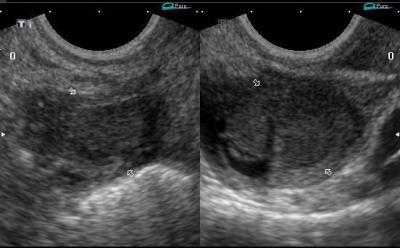

Трансабдоминальное ультразвуковое обследование и трансвагинальная эхография позволяет отличить доброкачественное образование от миомы. Наличие метастазов можно определить путем проведения томографических исследований (МРТ/КТ). Это обследование также назначают при лечении рака яичников за рубежом.